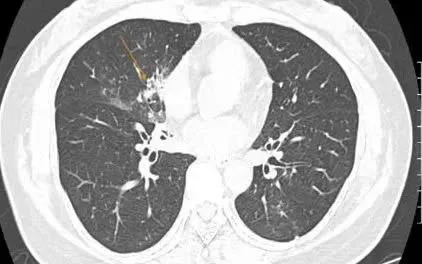

Tại Việt Nam và nhiều quốc gia trên thế giới vẫn tồn tại nghịch lý điều trị và phòng ngừa viêm phổi do phế cầu. TS.BS. Lê Thị Thu Hương, Trưởng Khoa Nội hô hấp - Bệnh viện Nhân dân Gia Định (TP Hồ Chí Minh) phân tích, chi phí điều trị một ca viêm phổi có thể lên tới 710 triệu đồng (chi phí điều trị tại Mỹ), chưa kể chi phí hồi phục chức năng và công sức chăm sóc của người nhà. Đối với những ca nguy kịch, chi phí điều trị có thể cao hơn gấp nhiều lần.

“Người lớn tuổi bị viêm phổi do phế cầu có thể trải qua hàng tháng trời trong phòng hồi sức tích cực. Sau khi xuất viện, người bệnh suy kiệt, suy giảm chức năng phổi và phụ thuộc rất lớn vào người chăm sóc” - TS.BS. Lê Thị Thu Hương chia sẻ thêm.